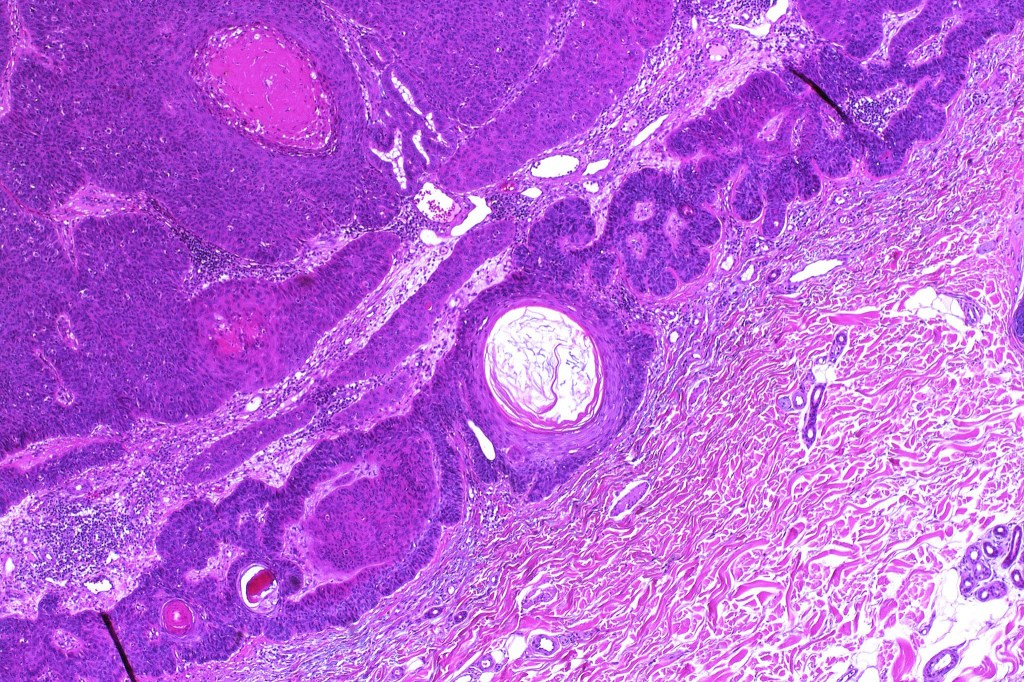

•Biphasic tumor combining squamous cell carcinoma and adenocarcinoma; the latter showing ductal and glandular differentiation

•Glands are lined by cuboidal to columnar epithelium

•Intracytoplasmic lumina sometimes evident

•Glandular foci show mucin

•Variable pleomorphism & mitotic activity but can be marked

•Perineural infiltration is common (up to 15% of cases)

For comparison an actholytic squamous cell carcinoma- in cases of doubt, IHC and special stains for mucin will resolve the problem.